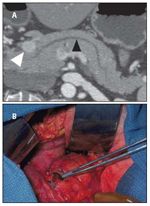

FIGURE 1

Pancreatic Insulinoma

The only potentially curative therapy for insulinomas is surgical removal. The cure rate and disease-specific survival can be as high as 100% after resection of sporadic insulinomas, as these tumors are generally (> 90%) benign.[7,8] Insulinomas are typically small (< 2 cm) and can be difficult to localize preoperatively. In addition, they lack a high density of type 2 somatostatin receptors, making somatostatin receptor scintigraphy (SRS, or octreotide scan) rarely helpful (in only 10% of cases). For most patients, pancreatic protocol computed tomography (CT) (Figure 1A) and endoscopic ultrasound (EUS) are the best preoperative tools for localization; they have a combined sensitivity of as high as 90%.[9] If the tumor cannot be localized preoperatively, measurement of the insulin gradient in the hepatic veins after selective intra-arterial calcium stimulation can localize the tumor in up to 87% of cases.[7,10] Furthermore, surgical exploration with intra-operative ultrasound and bimanual palpation has a 95% sensitivity in localizing these tumors, and in the authors' experience, the addition of preoperative calcium angiography to intra-operative ultrasound has been found to localize 100% of occult insulinomas.[7] Since the majority of insulinomas (80% to 90%) are typically small (< 2 cm), solitary, and benign, these tumors can be removed through enucleation rather than pancreatic resection (Figure 1B). Enucleation has the benefit of sparing normal pancreatic parenchyma as long as the integrity of the pancreatic duct is preserved. If enucleation is not possible, then pancreaticoduodenectomy for head tumors and central or distal pancreatectomy for body or tail tumors may be necessary. Laparoscopic enucleation is also becoming increasingly common. When tumors cannot be identified intra-operatively, a pancreatic biopsy is warranted, as the patient may have adult nesidioblastosis.[4] However, this diagnosis is controversial and the authors think that it is seldom, if ever, valid.